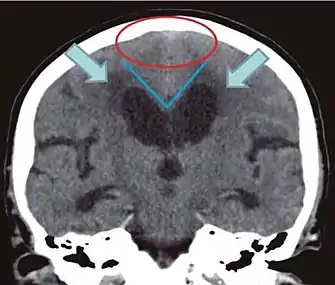

- Imaging from magnetic resonance imaging (MRI) or computed tomography (CT) is needed to demonstrate enlarged ventricles and no macroscopic obstruction to cerebrospinal fluid flow. Imaging should show an enlargement to at least one of the temporal horns of lateral ventricles, and impingement against the falx cerebri resulting in a callosal angle ≤ 90° on the coronal view, showing evidence of altered brain water content, or normal active flow (which is referred to as "flow void") at the cerebral aqueduct and fourth ventricle.

| Normal pressure hydrocephalus | Brain atrophy | |

|---|---|---|

| Preferable projection | Coronal plane at the level of the posterior commissure of the brain. | |

| Modality in this example | CT | MRI |

| CSF spaces over the convexity near the vertex (red ellipse | Narrowed convexity ("tight convexity") as well as medial cisterns | Widened vertex (red arrow) and medial cisterns (green arrow) |

| Callosal angle (blue V) | Acute angle | Obtuse angle |

| Most likely cause of leucoaraiosis (periventricular signal alterations, blue arrows |

Transependymal cerebrospinal fluid diapedesis | Vascular encephalopathy, in this case suggested by unilateral occurrence |